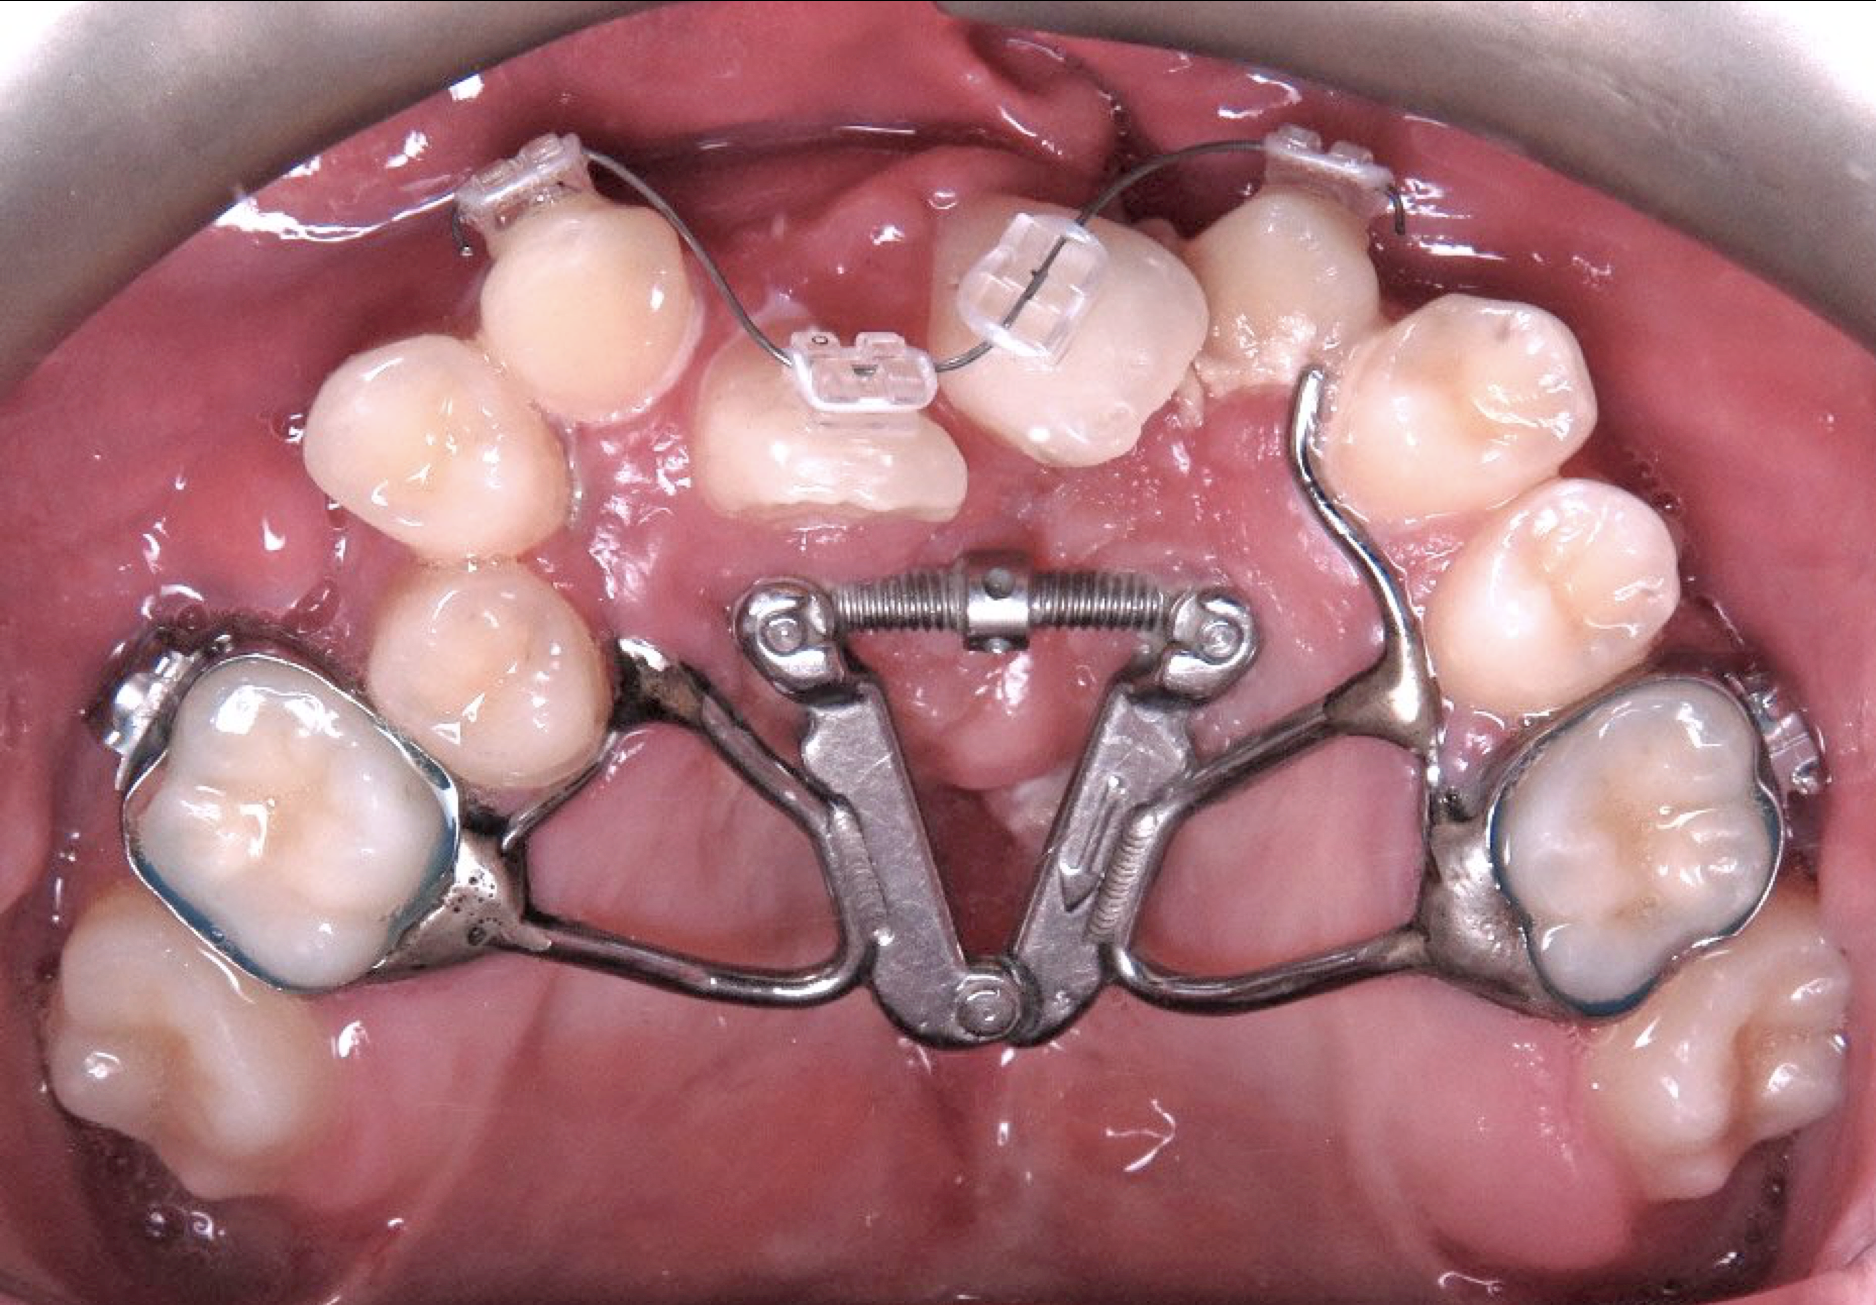

A palatal expander, also known as a maxillary expander or an orthodontic expander, is an orthodontic appliance used to gradually widen the upper jaw. It works by applying gentle, consistent pressure on the two halves of the maxilla, or upper jaw, which are joined together by a connective tissue structure known as the midpalatal suture. In children and adolescents, this suture is not yet fused, making it highly responsive to this type of controlled expansion.

The appliance is typically custom-made and fits over several upper back teeth. It features a central screw mechanism that the patient or a parent turns at home, following the orthodontist's instructions. Each turn activates the screw, moving the two halves of the appliance slightly apart, which in turn widens the palate. This process is slow and deliberate, designed to ensure the bone structure adapts naturally and without significant discomfort.

2. Placement of the Expander: Once the custom appliance is ready, the orthodontist will bond it to the patient's upper back teeth. The placement is quick and painless. The orthodontist will then provide detailed instructions on how to activate the expander, often using a small key to turn the central screw.